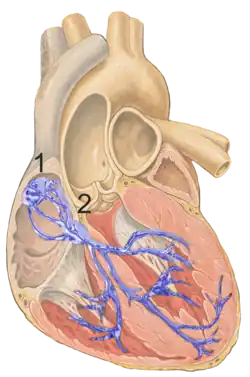

Image showing the conduction system of the heart. The AV node is labelled 2. | |